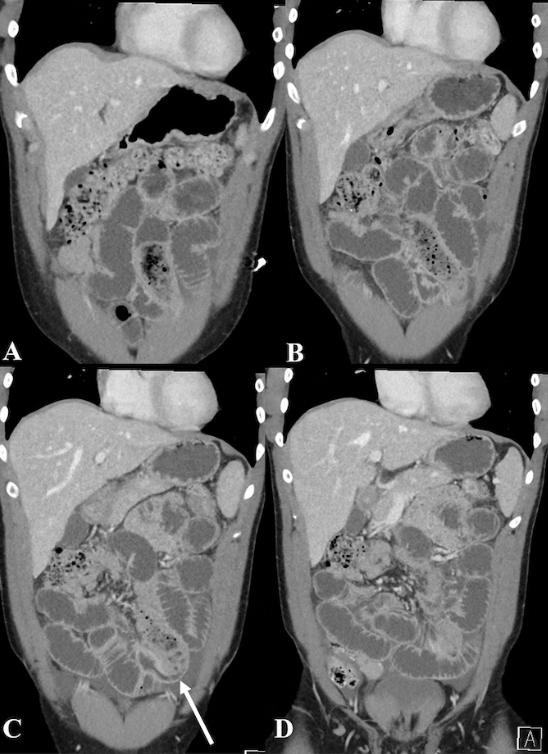

Läkarna som gjorde en datortomografi på en 34-årig man fick troligen en chock för livet efter att ha sett vad han fått i sig.

Mannen hade sökt läkarhjälp efter att ha haft stora smärtor och drabbats av magknip och kräkningar. Och så fick läkarna reda på att det var av goda skäl.

Han hade alltså haft problem med att gå på toaletten en hel dag eftersom han ätit en banan som han stoppat i en kondom, skriver New York Post och citerar tidningen Cureus.

Läkarna förklarade så småningom att mannen, som lidit av depression, hade kastat bananen i en kondom, varefter den hade konsumerats till följd av ett raseri.

Lyckligtvis lyckades läkarna operera kondomen ut genom ändtarmen. Mannen fick dock ligga kvar på sjukhus i ytterligare tre dagar innan han kunde skrivas ut.